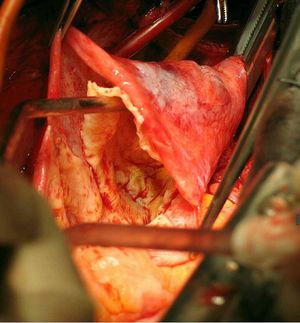

Aortic dissection is defined as separation of the layers within the aortic wall. Tears in the intimal layer result in the propagation of dissection (proximally or distally) secondary to blood entering the intima-media space. Mortality is still high despite advances in diagnostic and therapeutic modalities.Typical sign is sudden onset of severe chest pain that often has a tearing or ripping quality.